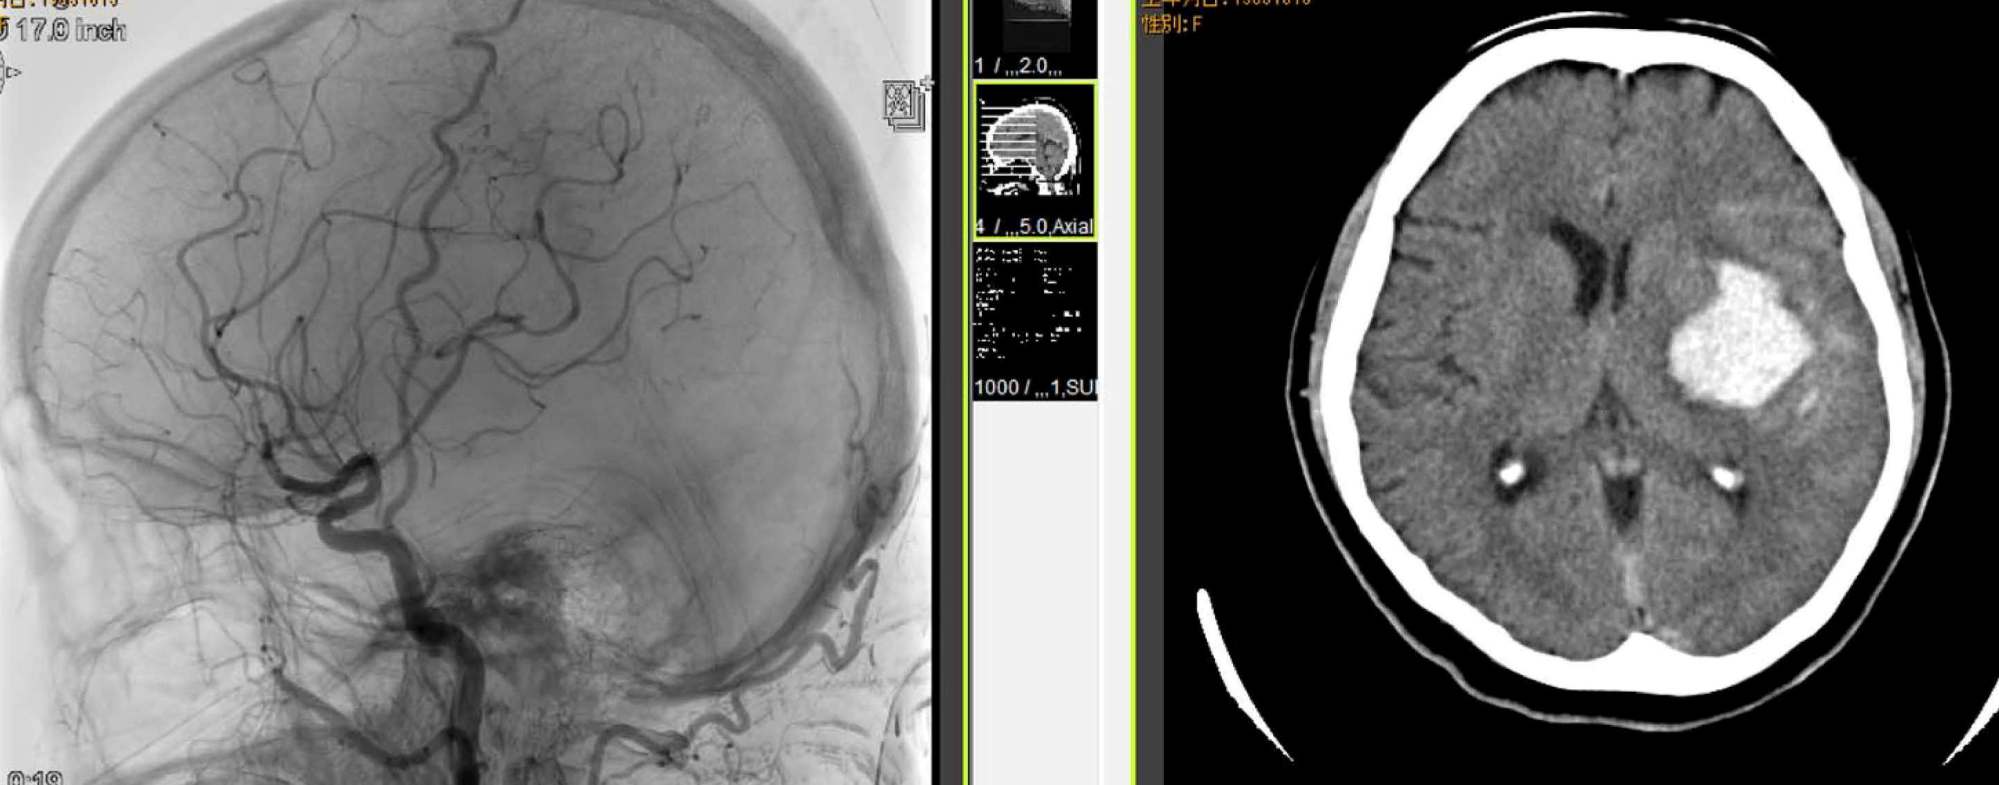

"三途土産"との闘い(脳出血後遺症の介護とリハビリ)の記録